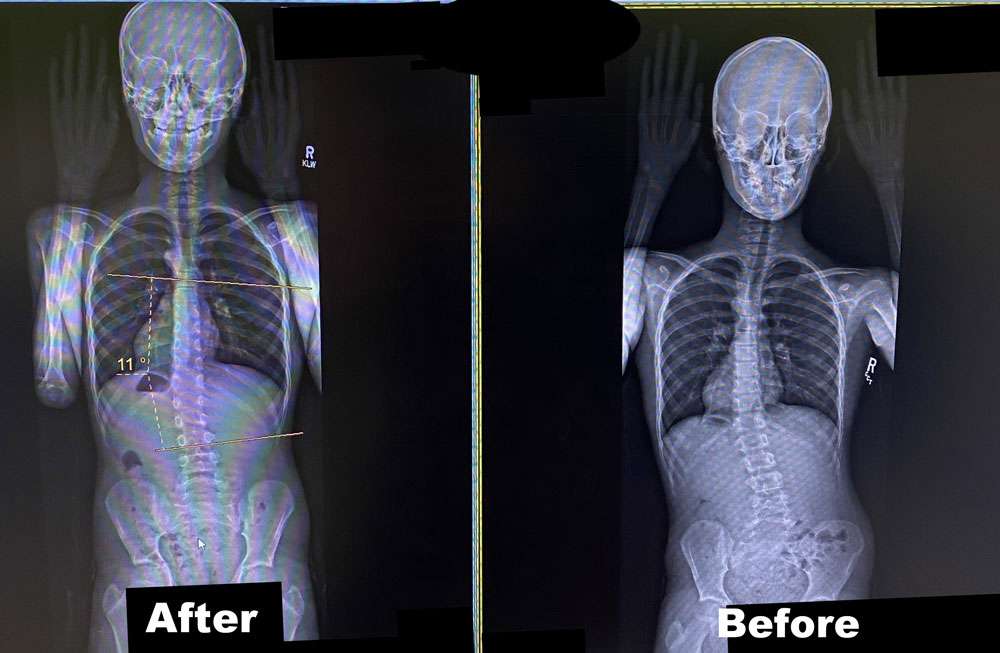

Scoliosis is measured on x-ray as a Cobb Angle. This measurement tells us how bad the scoliosis is and then guides us in how we treat it. Curves under 10 degrees usually aren’t considered scoliosis. Those curves 10-25 are called mild curves and we treat them with scoliosis specific exercise. Curves 25-45 degrees are treated with scoliosis specific exercise and bracing. Those above 45 degrees are usually surgical candidates. There is a measurement error of 3-5 degrees, which means to really have significant change, it needs to be above that.

Here are some examples of what can be done with scoliosis specific exercise with a variety of patients. The main goal of treatment is to STOP progression of the curve. With hard work and dedication we can also see reduction in the curve.